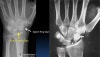

* Normal scapholunate space : The normal scapholunate space(arrowheads) is similar in width to other normal intercarpal joints(arrows).

* Scapholunate widening

Widening (arrowheads) of the scapholunate distance > 2 mm

The space is obviously wider than the other intercarpal spaces (arrows).

This results in the 'Terry Thomas sign'.

Widening if the scapholunate space indicates a tear injury of the scapholunate ligament.